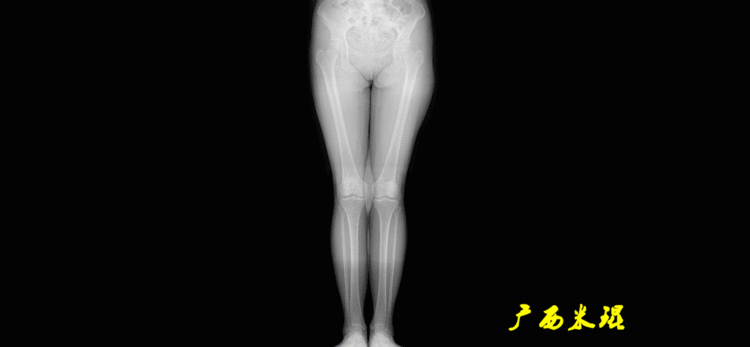

下肢力线及相关角度测量的前提是必须拍摄标准的站立位也就是负重位的下肢全长片。目前这样的照片都是放射科的技师在电脑上拼接出来的,大部分医院的DR都能够做到这一点。

患者直立于摄影架上,后背贴近摄影架,双手自然下垂,膝关节尽量伸直,足部与双肩同宽,要求投照时双髌骨朝正前方,通常患者双足尖应平行向前即可。

无论如何,拍摄出来的下肢全长片必须包含髋关节中心、膝关节中心及踝关节中心,否则对临床是无用的。有了一张下肢的全长照片,我们需要确定下肢关节的中心点,通过中心点画出下肢的各种轴线,然后利用轴线与关节线的相交得出各种所需要的角度。

机械轴要分前后位及侧位,站立前后位(也就是冠状面)股骨头中心与踝关节中心的连线通过膝关节中心,这是下肢的机械轴线,也就是下肢力线,常说Mikulicz线。冠状面的力线评估在临床工作中最常用、最基础、最重要。

最常见的下肢畸形发生于冠状面,即膝内外翻畸形,冠状面的对线异常通过应用“对线异常检验”进行分析,机械轴的偏移(MAD)表现为对线异常。

膝内翻是指下肢力线通过膝关节中心点内侧,距中点2mm以上,偏内超过15mm为显著膝内翻。膝外翻是指下肢力线通过膝关节中心点外侧,距中点2mm以上,偏外超过10mm为显著膝外翻。